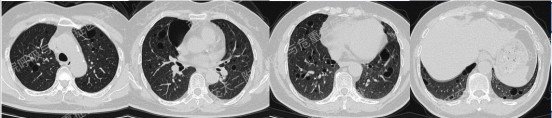

上图与Case 2比较相似,所以诊断LAM没有问题,还需进一步排查系散发型还是结节性硬化症累及。

影像学评估发现患者多系统受累(肝脏错构瘤、双肾血管平滑肌脂肪瘤、颅脑多发异常信号结节)。追问病史,患者本人无皮疹、癫痫及智力低下;患者儿子有面部皮脂腺瘤,无癫痫及智力低下,胸腹部CT未见异常,皮肤科已确诊结节性硬化症;患者女儿面容及智力均正常;建议患者进一步行TSC基因检测,结果回报TSC2突变,结节性硬化症诊断明确。